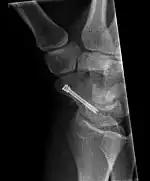

The scaphoid can be slow to heal because of the limited circulation to the bone. Fractures of the scaphoid must be recognized and treated quickly, as prompt treatment by immobilization or surgical fixation increases the likelihood of the bone healing in anatomic alignment, thus avoiding mal-union or non-union.[6] Delays may compromise healing. Failure of the fracture to heal ("non-union") will lead to post-traumatic osteoarthritis of the carpus.[1]: 189 One reason for this is because of the "tenuous" blood supply to the proximal segment.[3] Even rapidly immobilized fractures may require surgical treatment, including use of a headless compression screw such as the Herbert screw to bind the two halves together.

Scaphoid fractures may be difficult to diagnose via plain x-ray. A repeat x-ray may be required at a later date, as might cross-sectional imaging via MRI or CT scan.[6]